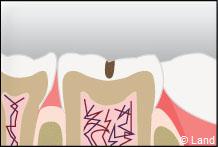

Les traitements possibles pour les stades de la carie où seuls l’émail et la dentine sont touchés, peuvent se faire au composite.

Si la cavité de carie est trop importante, il peut poser des problèmes d’étanchéité avec le temps.